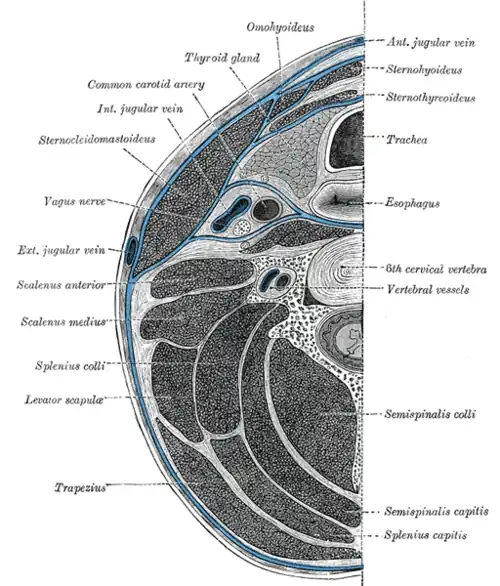

Die Halsfaszie gliedert mit ihren drei Blättern den Hals in mehrere Bereiche und bedeckt die Muskulatur des Halses. Daneben werden die verschiedenen Halseingeweide und die Leitungsbahnen des Halses von eigenen bindegewebigen Strukturen bedeckt, der Eingeweidefaszie und der Vagina carotica.[5][6]

Das oberflächliche Blatt (die Lamina superficialis) umhüllt als Teil der oberflächlichen Körperfaszie den gesamten vorderen Hals, bedeckt den Musculus sternocleidomastoideus und die Glandula parotidea. Einzig das Platysma und epifasziale Venen und Nerven liegen noch oberhalb dieser Faszie. Sie geht am Unterkiefer aus der Fascia parotideomasseterica hervor, geht nach unten in die Brustfaszie und nackenwärts in die Fascia nuchae über.[5][6]

Das mittlere Blatt, die Lamina pretrachealis beginnt etwa am Zungenbein und erstreckt sich bis zum Brustbein und zum Schlüsselbein. Dabei wird sie nach unten hin immer breiter und ist besonders fest in dem Bereich, wo sie die infrahyoidale Muskulatur bedeckt. Sie ist mit der Vagina carotica verwachsen, der Bindegewebshülle, die wichtige Leitungsbahnen wie die Halsschlagader, die Vena jugularis interna und den Vagusnerv umhüllt.[5][6]

Unter der Lamina pretrachealis liegt die Eingeweidefaszie, die die Halseingeweide (oder Halsorgane[7]), nämlich Kehlkopf, Rachen, Schilddrüse, Luft- und Speiseröhre, bedeckt.[5][6]

Das tiefe Blatt (Lamina prevertebralis) der Halsfaszie liegt direkt vor der Wirbelsäule und spaltet sich nach unten hin auf, so dass sie die Skalenusmuskeln und die prevertebrale Muskulatur, die autochthone Nackenmuskulatur und dem Musculus levator scapulae umhüllt. Sie reicht von der Schädelbasis bis etwa zum dritten Brustwirbel, wo sie in die Fascia endothoracica übergeht. Sie bedeckt außerdem den Truncus sympathicus mit den drei Halsganglien, den Plexus brachialis, die Arteria subclavia und den Nervus phrenicus.[5][6]

Muskulatur

Die Muskulatur des Halses lässt sich in verschiedene Gruppen einteilen. Zum einen sind dies die infrahyoidale Muskulatur, bestehend aus Musculus sternohyoideus, Musculus sternothyroideus, Musculus thyrohyoideus und Musculus omohyoideus. Diese Muskeln sind allesamt für das Schlucken von Bedeutung. Sie verlagern allesamt das Zungenbein nach unten und – bis auf den Musculus thyrohyoideus – außerdem den Kehlkopf und spielen so auch bei der Phonation eine Rolle. Der Musculus thyrohyoideus hingegen verlagert den Kehlkopf nach oben, sofern das Zungenbein fixiert ist. Der Musculus omohyoideus spannt außerdem die Lamina pretrachealis der Halsfaszie, mit der er über seine Zwischensehne verwachsen ist.[8][9]

Den Gegenpart zur infrahyoidalen Muskulatur bildet die suprahyoidale Muskulatur mit dem Musculus digastricus, Musculus geniohyoideus, Musculus mylohyoideus und dem Musculus stylohyoideus. Diese Muskeln heben das Zungenbein beim Schlucken nach oben und unterstützen darüber hinaus die Kieferöffnung.[8][9]

Die Gruppe der tiefen Halsmuskeln bildet die prävertebrale Muskulatur, die sich aus dem Musculus longus capitis, dem Musculus longus colli, dem Musculus rectus capitis anterior und aus dem Musculus rectus capitis lateralis zusammensetzt. Sie können die Halswirbelsäule drehen, bzw. bei beidseitiger Aktion nach vorne beugen, oder den Kopf drehen, zur Seite oder nach vorn beugen.[8][9]

Daneben kann man noch die Musculi scaleni („Treppenmuskeln“) unterscheiden, die aus Musculus scalenus anterior, medius, posterior und bei manchen Menschen auch aus einem Musculus scalenus minimus besteht. Diese Muskeln wirken als Atemhilfsmuskeln, oder können – wenn die Rippen fixiert sind – die Halswirbelsäule zur Seite oder nach vorne beugen.[8][9]

Der Musculus sternocleidomastoideus und das oberflächlich gelegene Platysma lassen sich keiner Gruppe zuordnen.[8][9] Im Nacken liegen außerdem die Nackenmuskeln, die aber zur autochthonen Rückenmuskulatur zählen.[8]